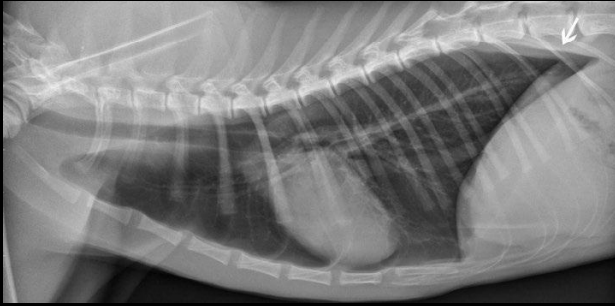

Radiografia laterolateral

Dependiendo de la posición los gases van a un lado o a otro: Decúbito lateral derecho Radiografía Lateral

- Gas en fundus

- Se ve mejor cola del bazo

- Mayor separación de siluetas renales

Decúbito lateral izquierdo

- Gas en píloro

- Mejor visualización delduodeno